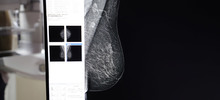

Alcaldía de Cali ratificó su compromiso para la detección temprana de cáncer